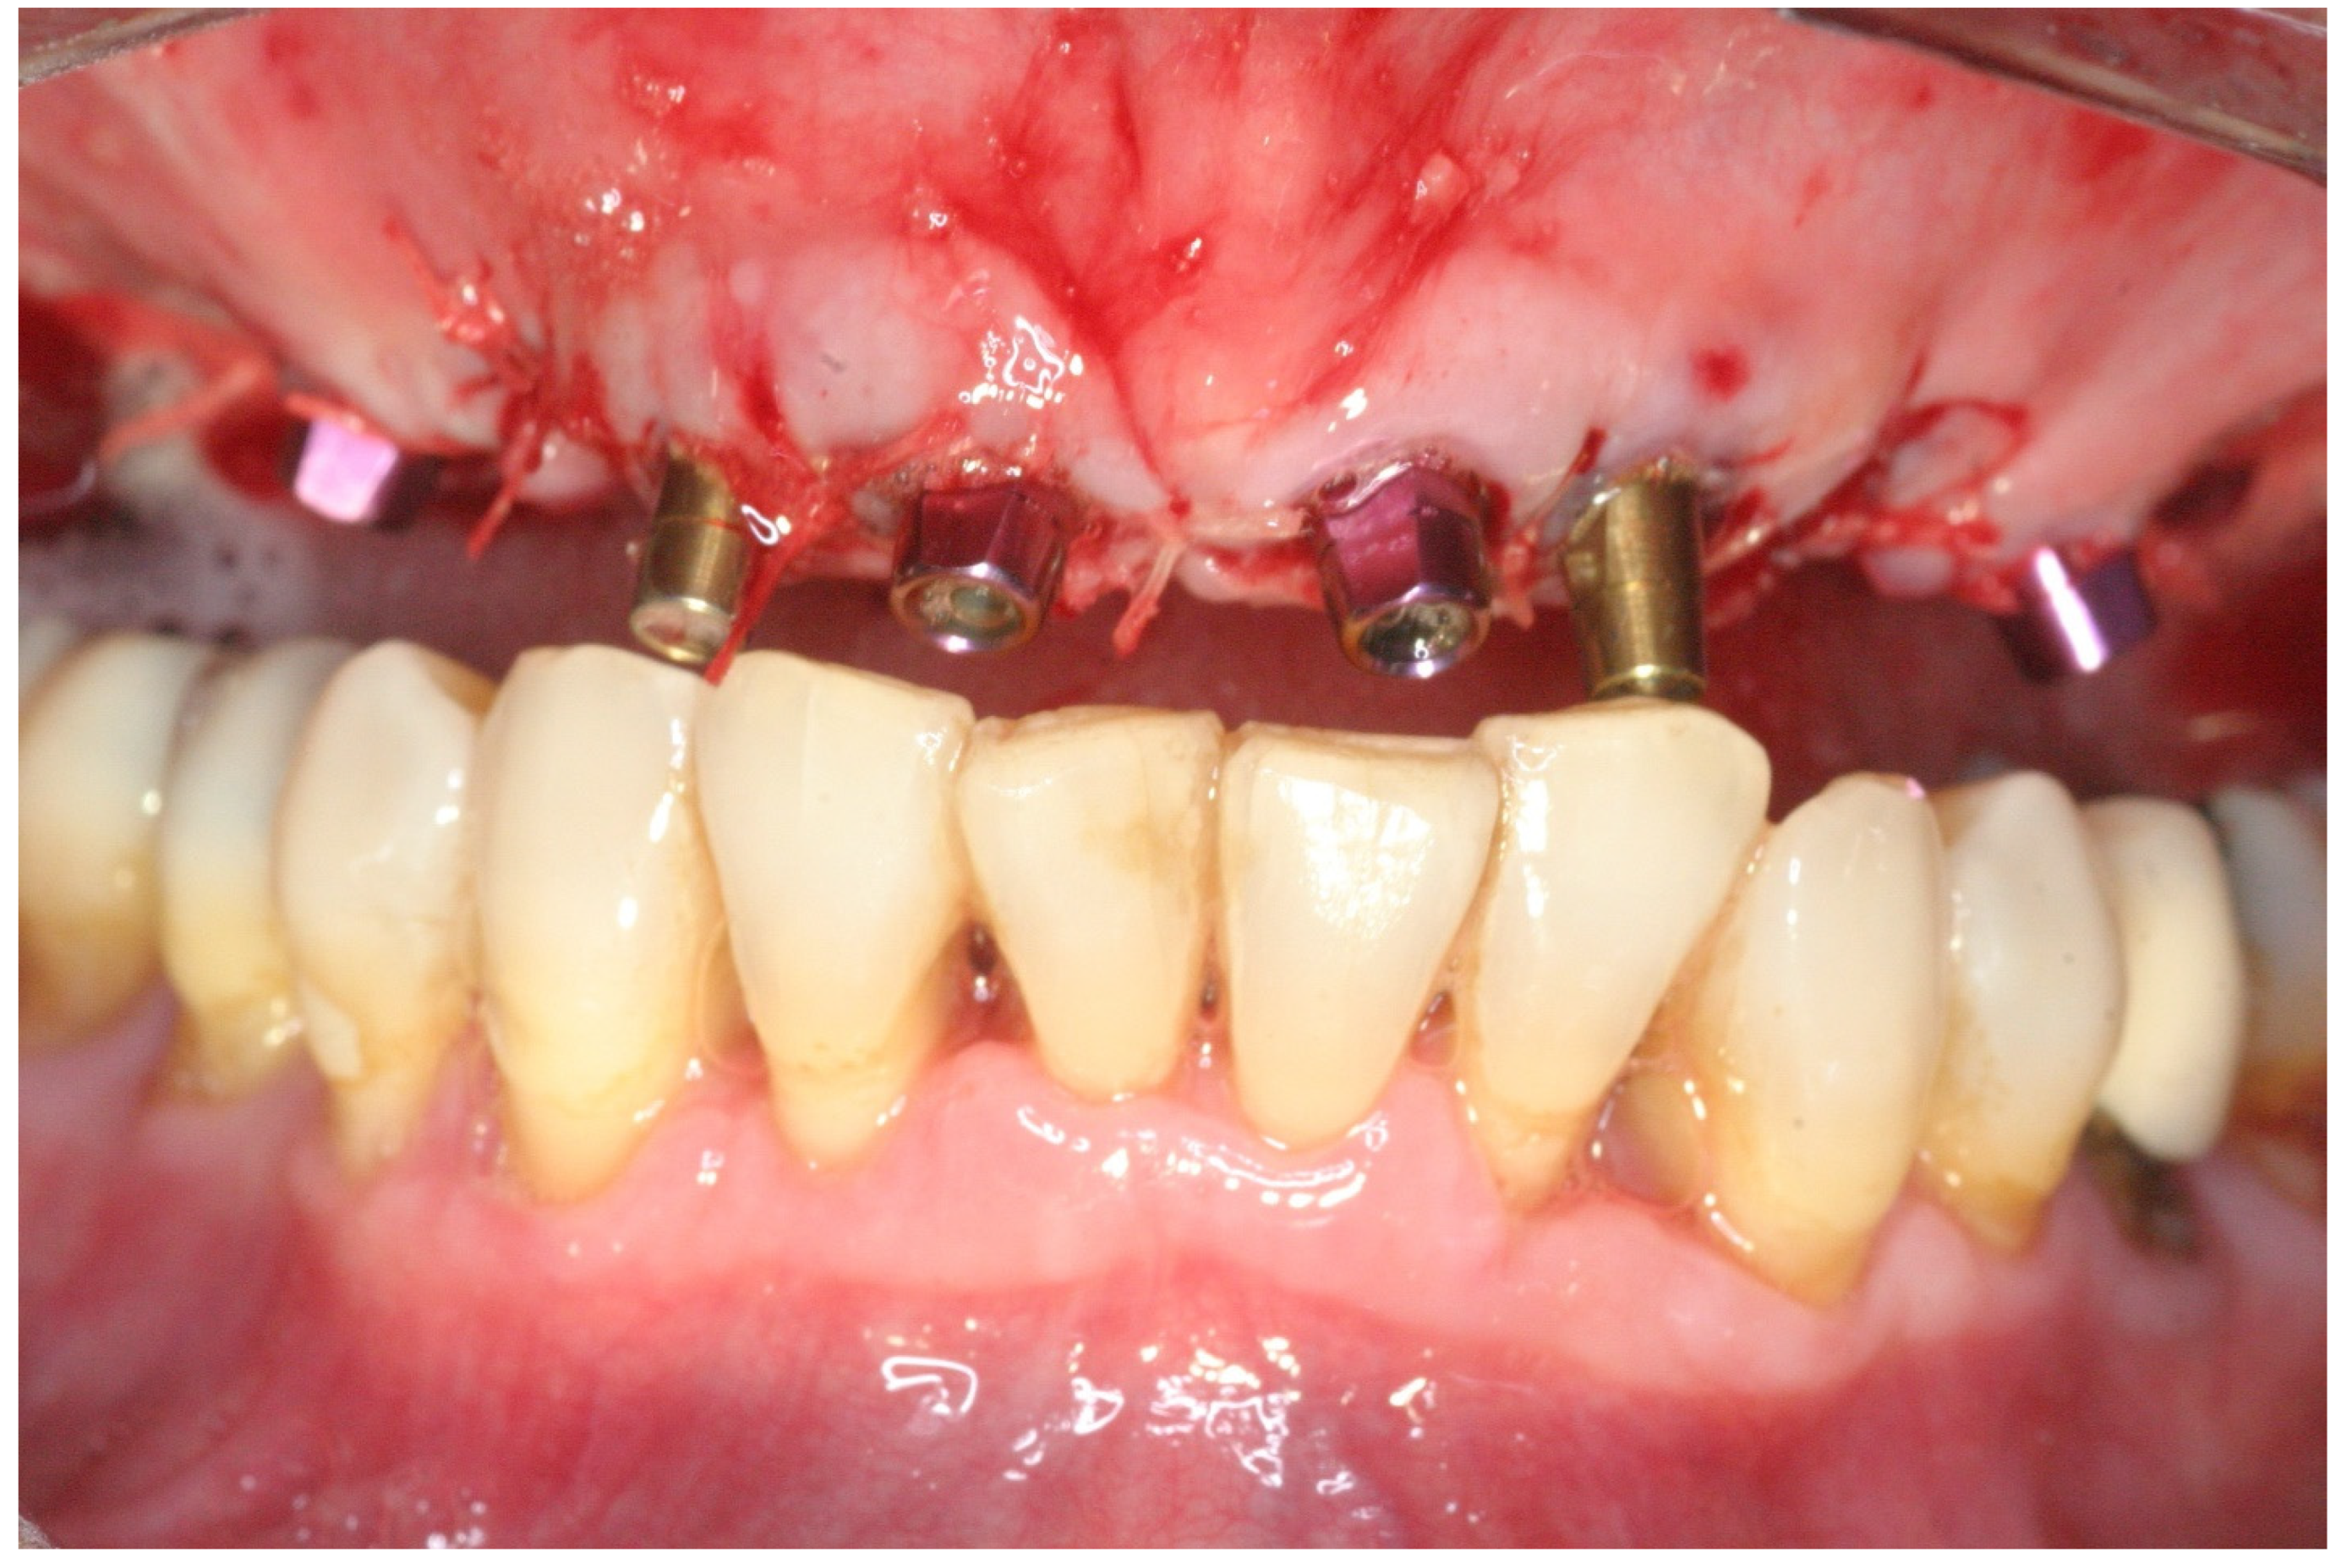

2.2. Surgical Treatment

2.3. Prosthetic Protocol